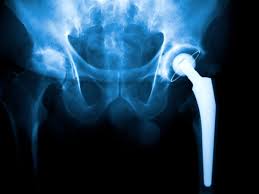

Hip pain caused by arthritis, avascular necrosis, or severe joint damage can significantly limit daily activities and independence. In Gadchiroli, many patients now prefer robotic hip replacement because it offers higher precision, better implant positioning, and faster recovery. This advanced surgical approach helps restore mobility while reducing pain and long-term complications. Therefore, choosing the right hospital and surgical expertise becomes essential for successful outcomes and long-lasting relief.

Hip replacement becomes necessary when conservative treatments such as medication, physiotherapy, and lifestyle modification fail to relieve pain. Conditions like advanced osteoarthritis, rheumatoid arthritis, and avascular necrosis often damage the hip joint beyond repair. Robotic hip replacement allows surgeons to customize the procedure based on the patient’s anatomy. Moreover, this personalization helps preserve healthy bone and ensures balanced joint movement after surgery.

Robotic systems use pre-operative imaging to create a detailed 3D model of the hip joint. This technology helps surgeons plan implant size, position, and alignment before entering the operating room. At Varunam Hospital, Dr. Utsav Agrawal oversees the integration of robotic guidance with surgical expertise. Therefore, patients in Gadchiroli benefit from improved leg length balance, reduced implant wear, and better long-term joint stability.

Robotic hip replacement offers durable pain relief and improved joint function for many years. Accurate implant placement reduces the risk of dislocation and uneven wear. Moreover, patients experience improved posture, smoother walking patterns, and better quality of life. For residents of Gadchiroli, access to robotic surgery at Varunam Hospital means receiving advanced orthopedic care close to home.